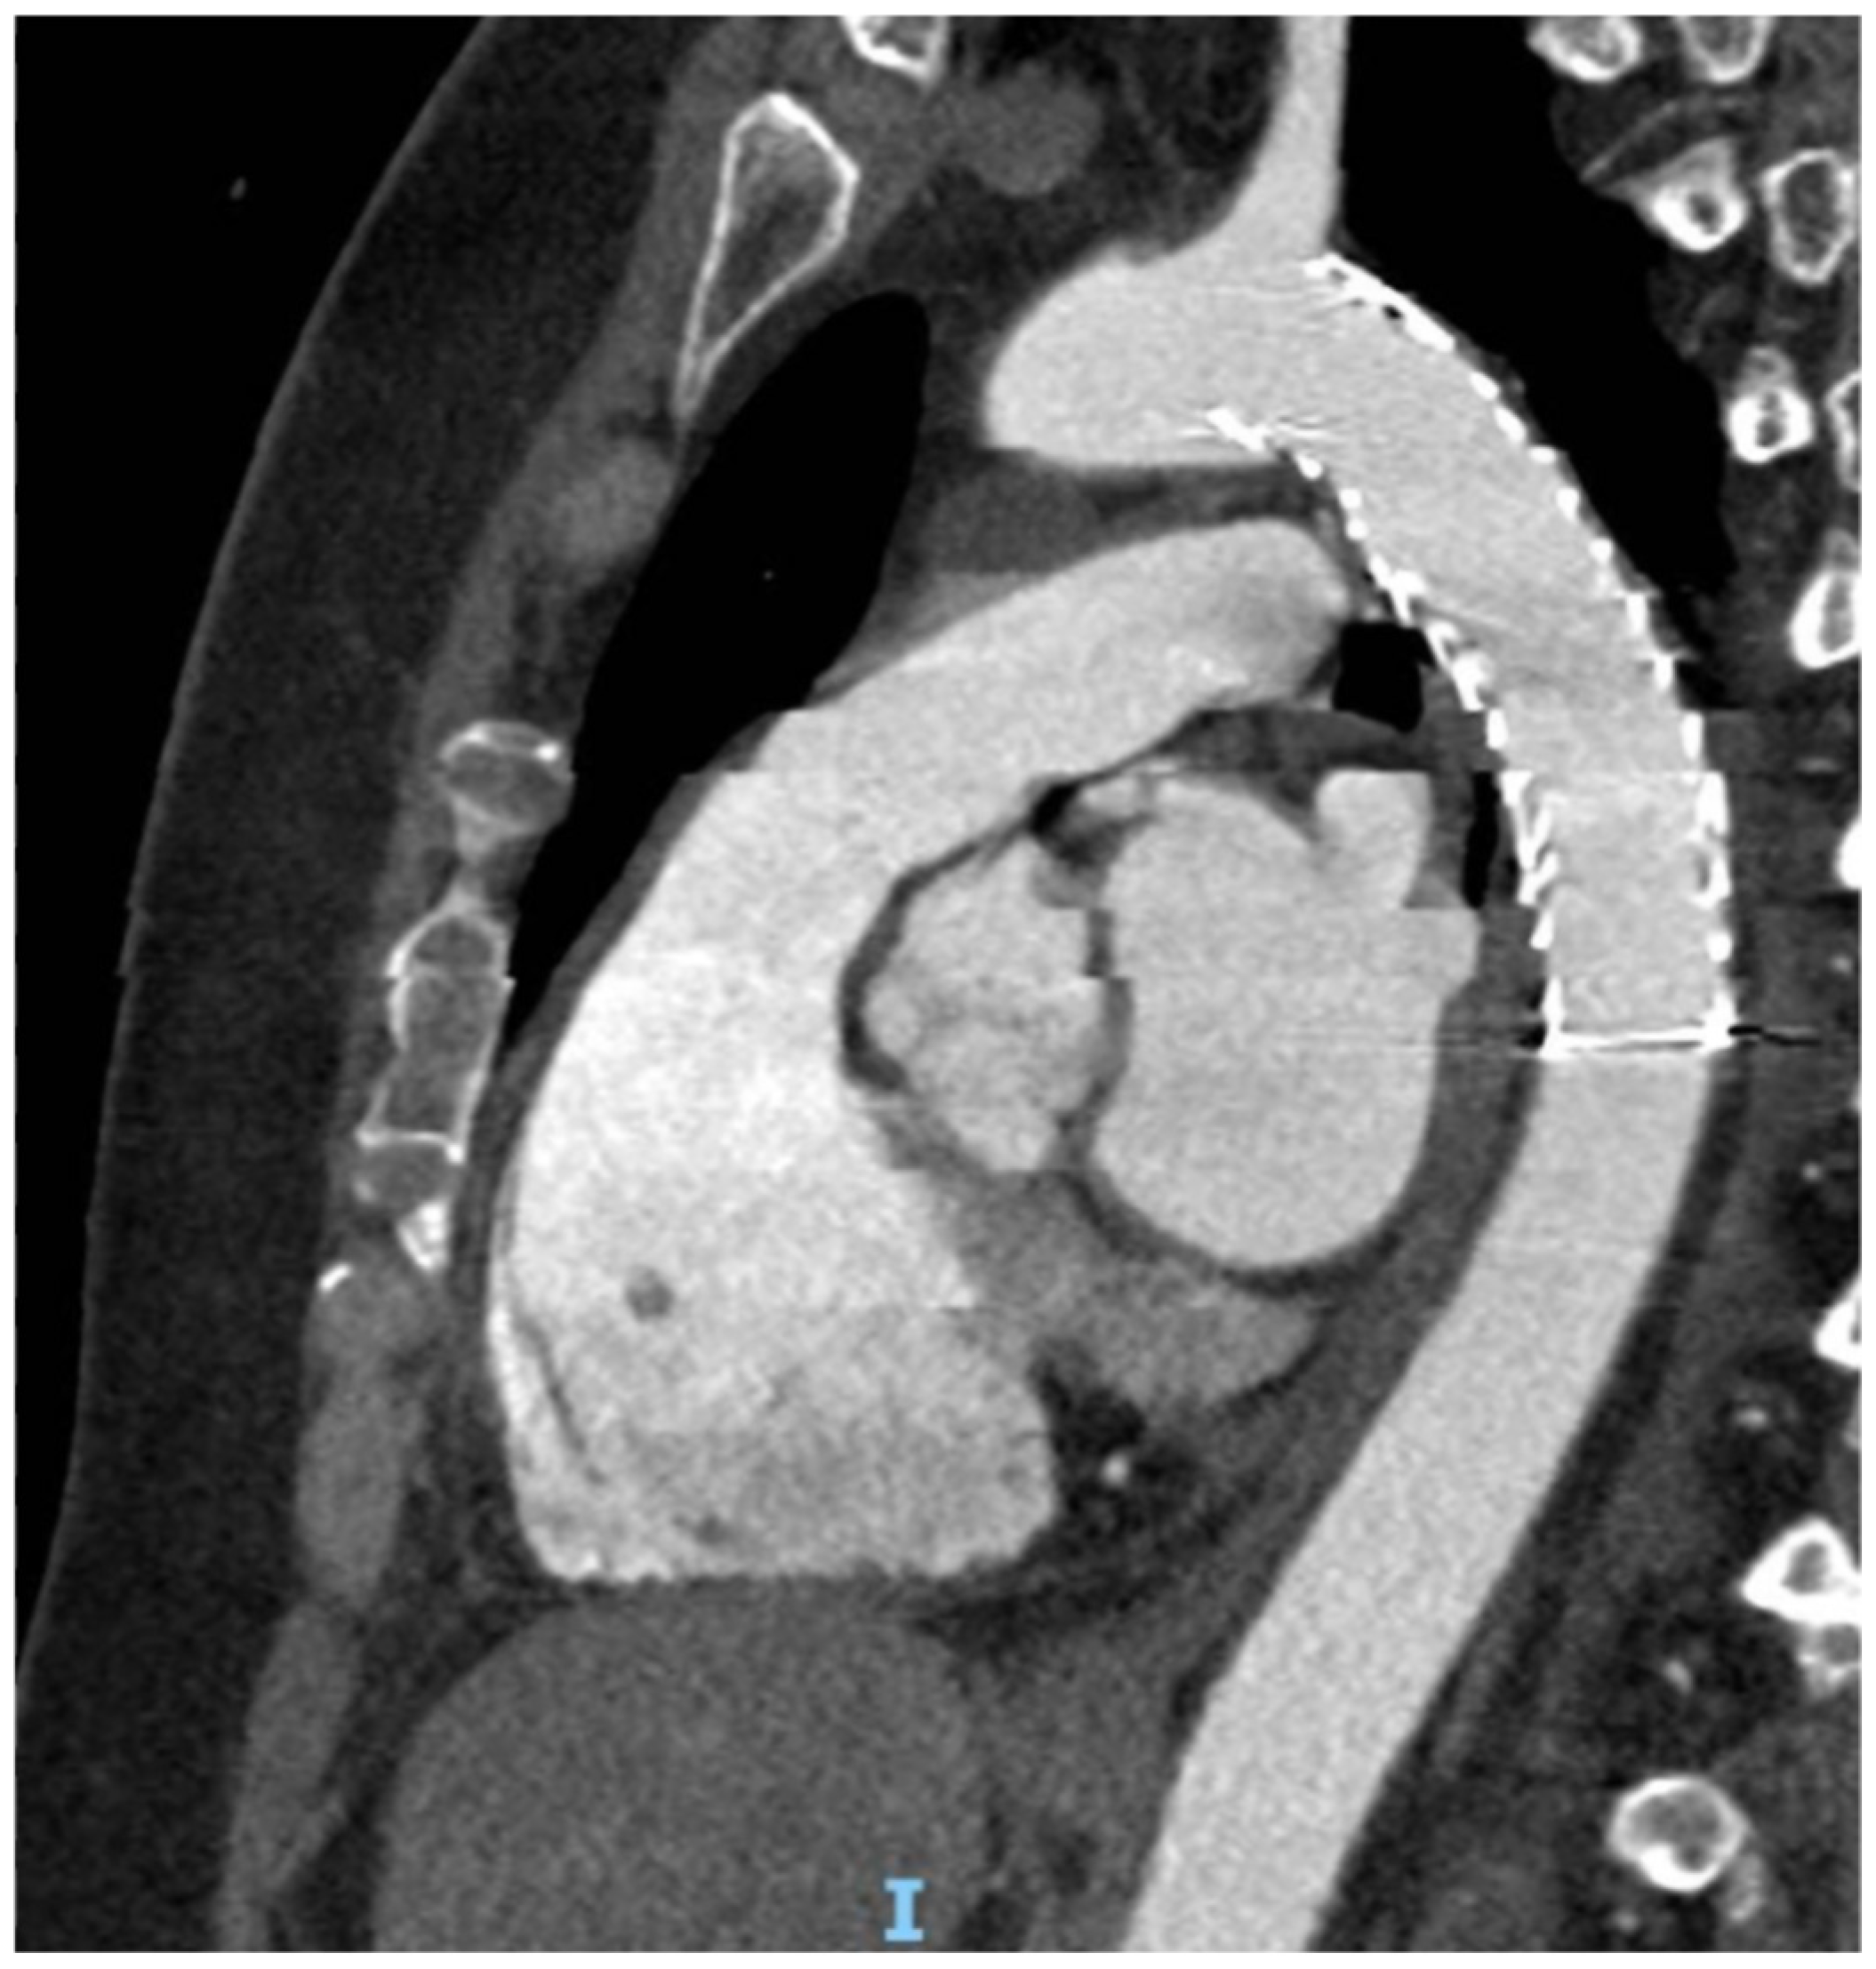

Endovascular Repair of Blunt Aortic Trauma: A Multidisciplinary Approach and a Retrospective Multicenter Study

- Type I: intimal tear

- Type II: intramural hematoma

- Type III: pseudoaneurysm

- Type IV: rupture

| Endovascular treatment | 40 (88.8%) |